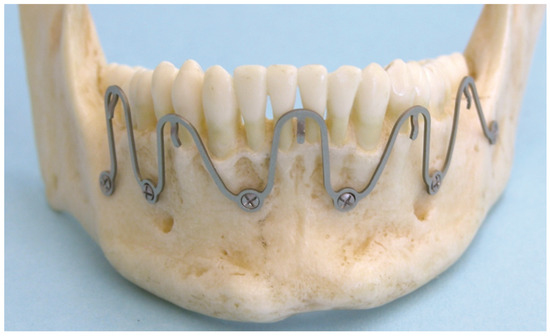

2.3. Matrix Wave System—Final Design and Technical Description

3.1. Matrix Wave Plate—Segmentation and Malleability